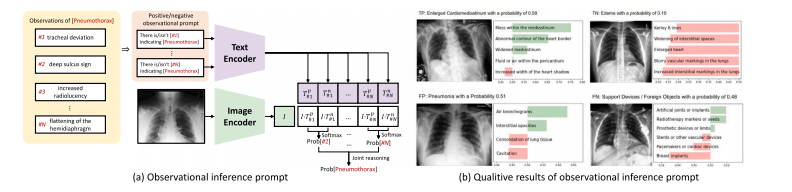

Fig. 11. Overview of Xplainer. (a) Illustration of the observational inference prompt proposed by Xplainer. The diagnosis of Pneumothorax is demonstrated here, while otherpotential diseases can also be implemented in this way. (b) The qualitative results of Xplainer.

图11:Xplainer概述。(a)Xplainer提出的观察性推理提示图示。此处展示了气胸的诊断过程,其他潜在疾病也可以通过这种方式来实现诊断。(b)Xplainer的定性结果。